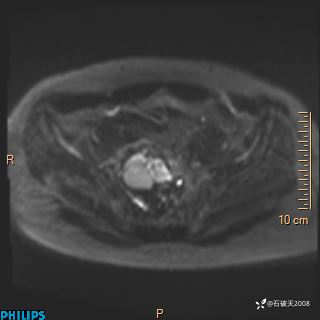

2023年3月份MRI影像

增强轴位